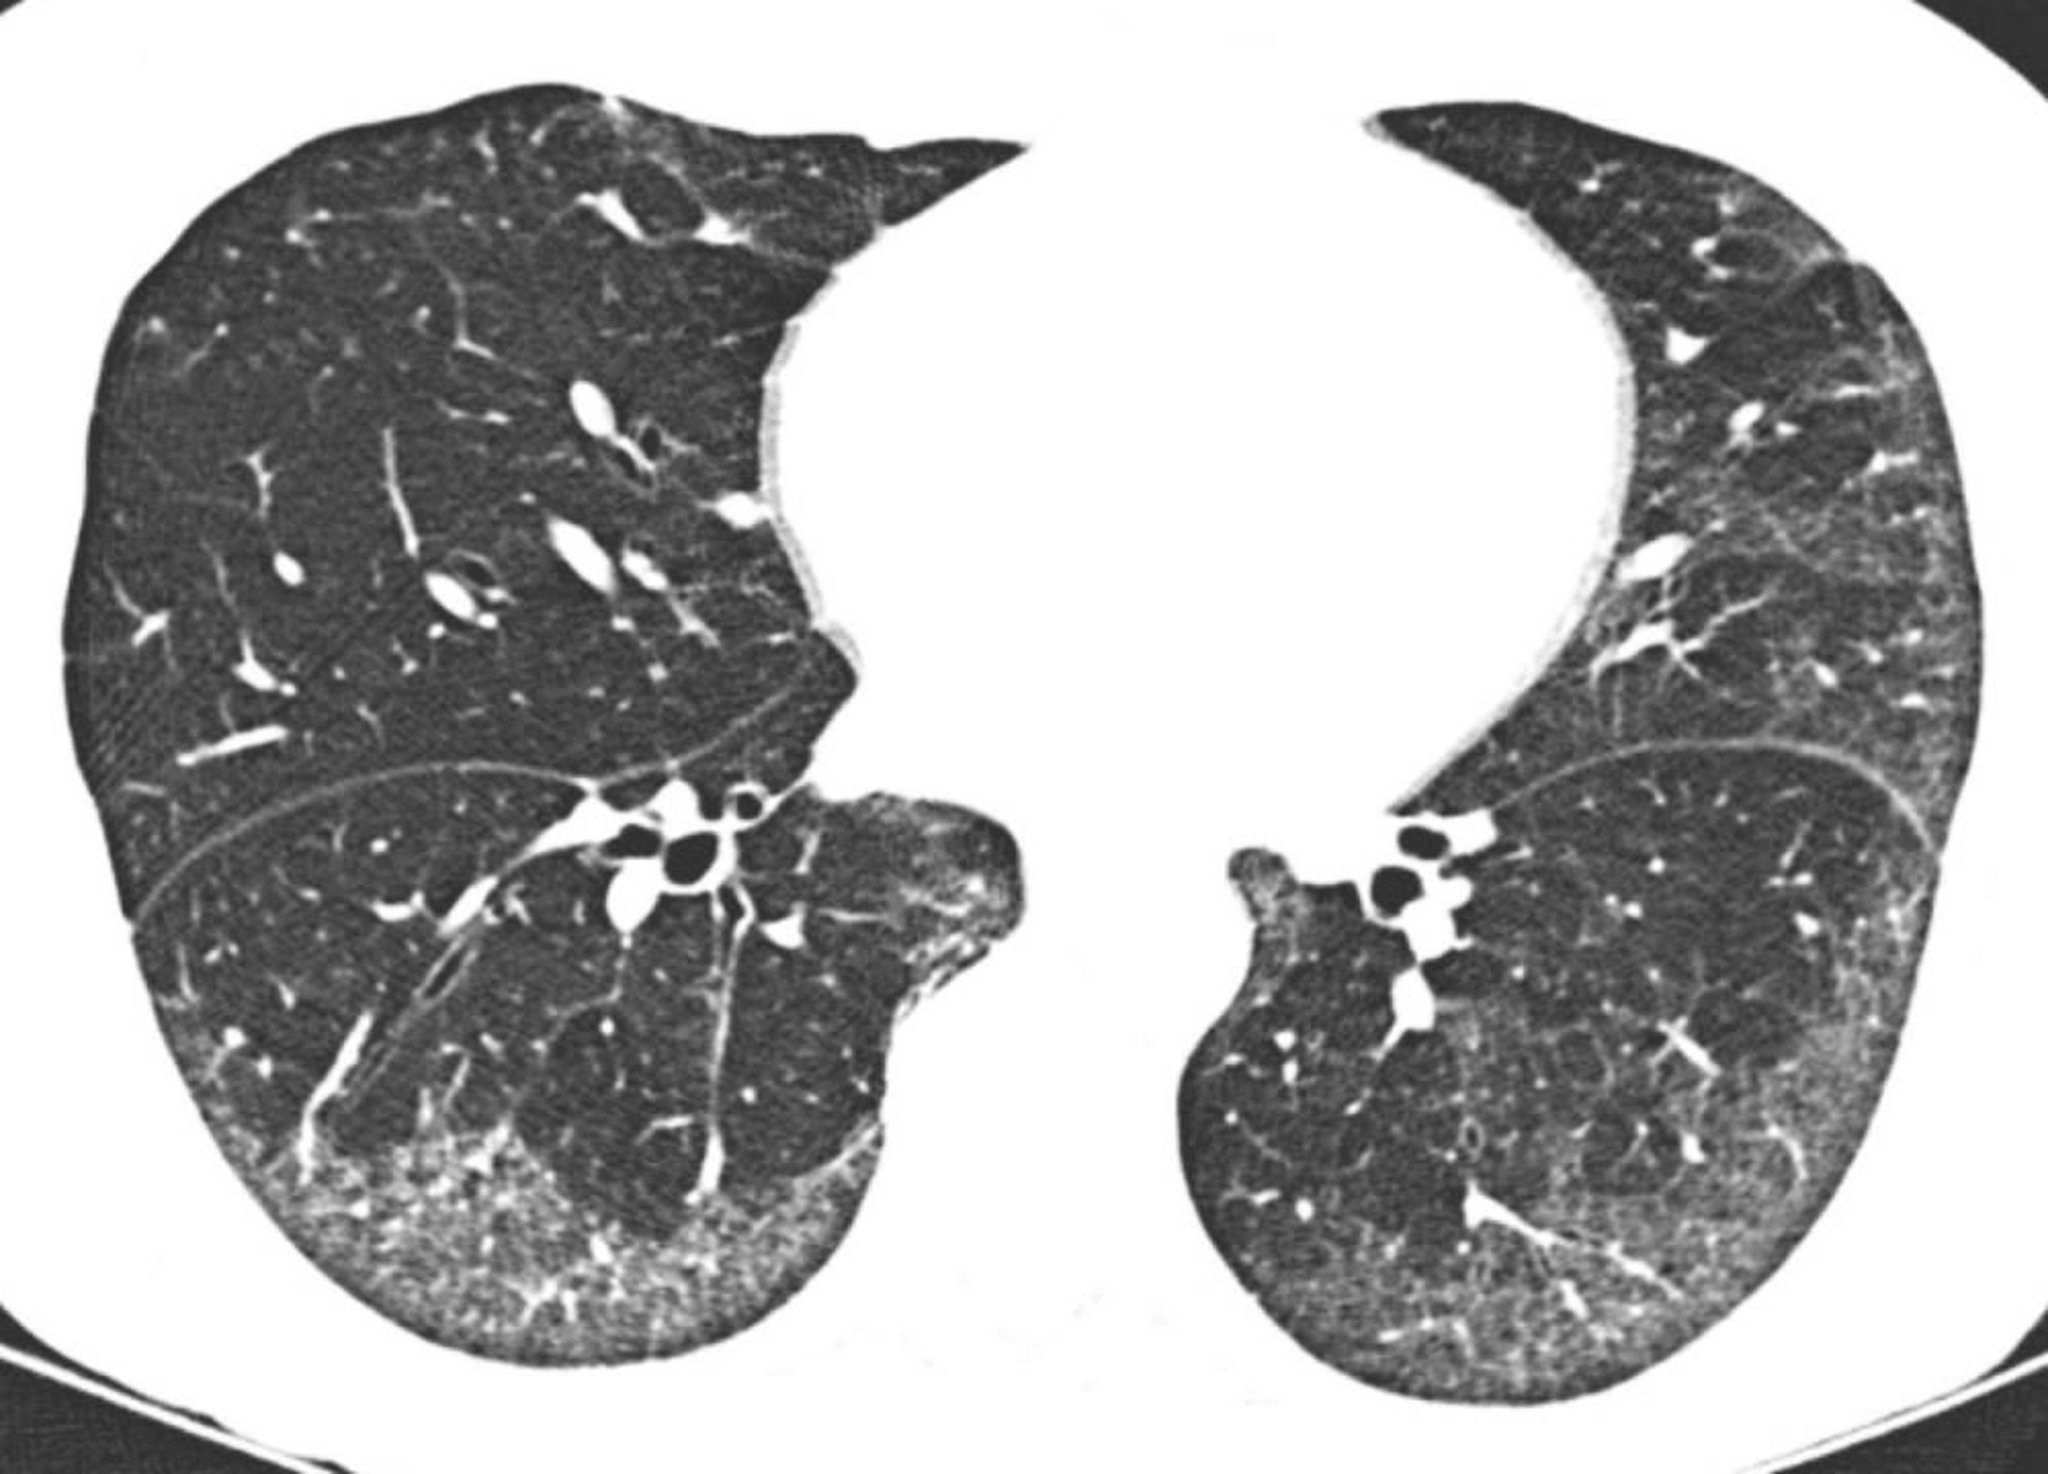

High-resolution CT shows predominantly subpleural and basilar ground-glass opacities. The relative sparing of the lung directly beneath the pleural surfaces is typical in nonspecific interstitial pneumonia.

Image courtesy of Harold R. Collard, MD.